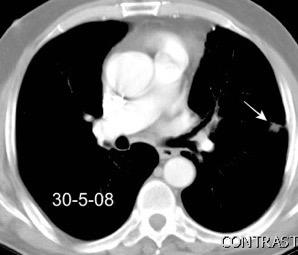

Tromboembolismo pulmonar.

Frecuencia del derrame:

Rx: 32%. TC: 47%

Unilateral. 85%

< 1/3 del hemitórax: 90%

Todos exudados

58% con eritrocitos

21% tabicación lo que causa demora en el diagnóstico

TEP. Empiema pleural. Atelectasia redonda